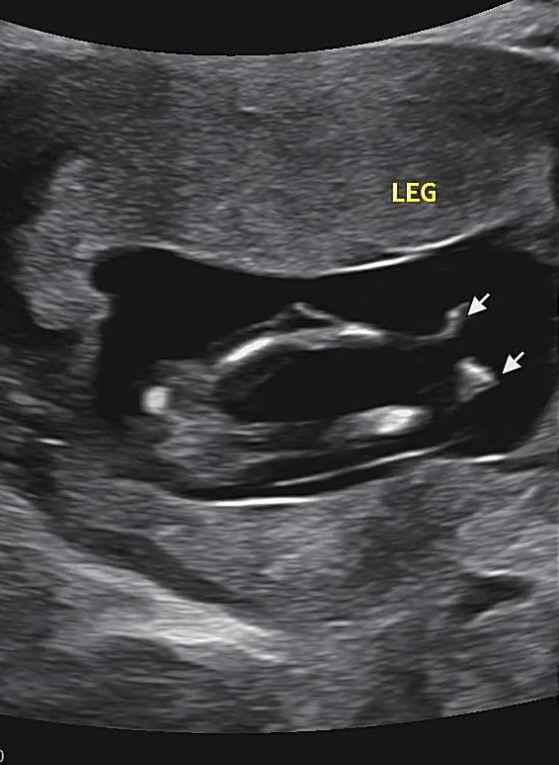

12주인데 다리사이로 머가 보이는걸까요

아직은 너뮤 이르긴하지만 궁금해요! 의견주새요

중간에🌶보여요....